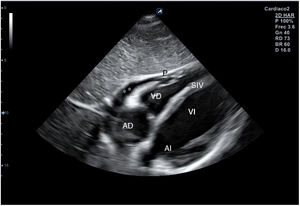

El plano paraesternal de eje largo se obtiene con la sonda sobre el segundo o el tercer espacio intercostal izquierdo, próxima al esternón y perpendicular a la piel, sobre una línea que une el hombro derecho con la cadera izquierda (fig. 2). La zona más próxima al transductor es la pared anterior del ventrículo derecho (VD), siendo también visibles la válvula mitral, la válvula aórtica (valva coronaria derecha y no coronaria), el ventrículo izquierdo (VI), la aurícula izquierda (AI), el tracto de salida del VI con la raíz aórtica, parte de la aorta ascendente y el pericardio. Si el corte es bueno, el septo interventricular anterior y la pared anterior de la aorta deben estar alineadas al mismo nivel y dispuestas de forma perpendicular al plano de estudio. La válvula mitral aparece en el centro de la imagen, de forma que su valva anterior se continúa con la pared posterior de la aorta. La aorta descendente puede verse también por detrás de la AI (fig. 3).

Las medidas a obtener en este plano son: la raíz aórtica (al principio de la sístole ventricular, con las valvas abiertas), la AI (al final de la sístole ventricular), el septo interventricular anterior y la pared posterior (en diástole) y el diámetro diastólico del VI (en telediástole y posición medioventricular, con apertura máxima).